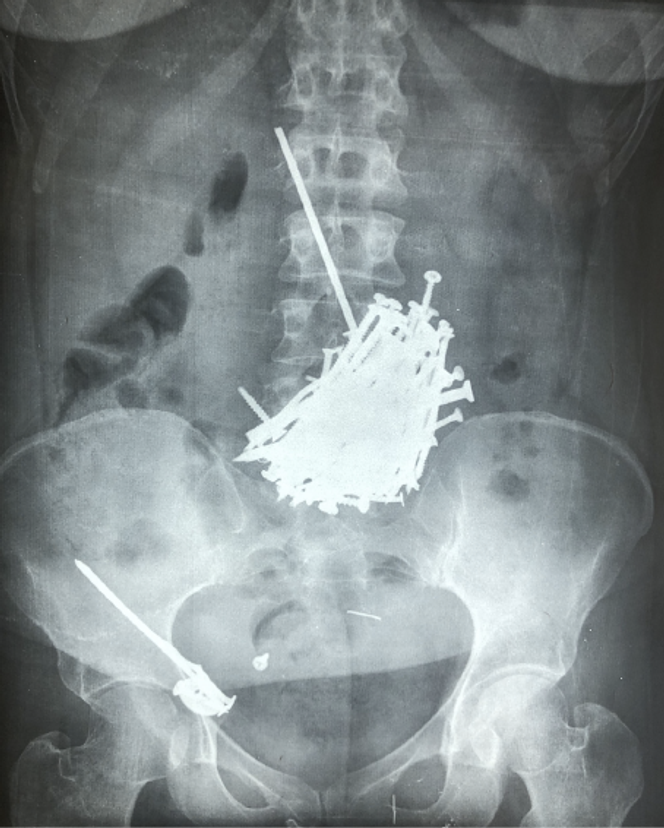

Multiples clous métalliques dans l’estomac à la radiographie abdominale.

La radiographie standard de l’abdomen a révélé la présence de nombreux corps étrangers opaques dans l’estomac du patient.

De nombreux corps métalliques ont été extraits de l’estomac.

Lors de l’intervention chirurgicale, des clés, des clous, des barreaux de fer, des aiguilles, des coupe-ongles, des lames et des cure-oreilles ont été retirés avec succès de son estomac. Au total, 120 corps étrangers métalliques sont extraits. Fait remarquable, ce patient n’a présenté aucune complication, notamment aucune perforation digestive, malgré la présence prolongée de ces nombreux objets tranchants, une situation inhabituelle.